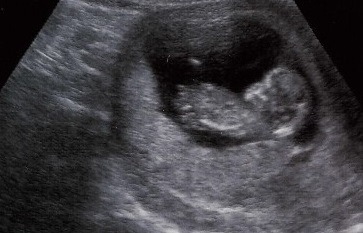

Orfeus heeft de mogelijkheid om echo apparatuur te koppelen met Orfeus 1e lijn en Orfeus 2e lijn. Met deze koppeling is het mogelijk om de meetwaarden en/of beelden van het echo apparaat rechtstreeks naar Orfeus te sturen en deze in te lezen in het desbetreffende zwangerschapsdossier. Handmatig overnemen van gegevens, tijdrovend en foutgevoelig, behoort daarmee tot de verleden tijd.

De mogelijkheid om te koppelen en meetwaarden en/of beelden naar Orfeus te sturen, hangt af van de specificaties van je echo apparaat. De eerste stap is dan ook om de specificaties bij je leverancier op te vragen en aan ons door te geven.